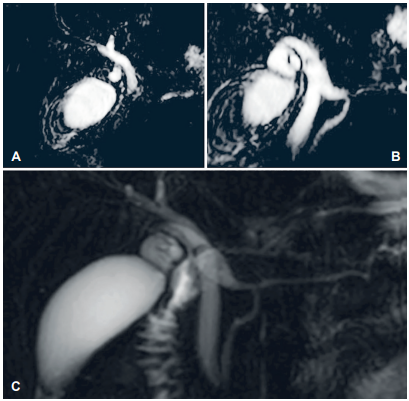

Adicionalmente fue valorada por el servicio de gastroenterología, quienes consideraron necesario realizar pancreatoscopia más litotripsia por spyglass por la pancreatolitiasis. En la colangiorresonancia (Figura 2) se evidenció dilatación del conducto cístico, con imagen hipointensa en su interior que sugería la presencia de cálculo, con terminación en el conducto pancreático; dilatación del conducto pancreático de Santorini a nivel de la papila menor, sin cálculo en su interior; vía biliar intrahepática y colédoco levemente dilatados. Dada la posible alteración anatómica de los conductos pancreáticos sin cálculos en su interior, se canceló la pancreatoscopia más litotripsia y, para evaluar con mayor claridad la anatomía, se solicitó una resonancia con contraste hepatoespecífico, con la que se descartó la presencia de cálculos y los hallazgos adicionales sugirieron un posible Santorinocele.

Figura 2. Colangioresonancia. A. Se observa la vía biliar intra y extrahepática levemente dilatada. B-C. Lesión hipodensa en conducto cístico sospechoso de cálculo y dilatación del Santorini (Santorinocele?).